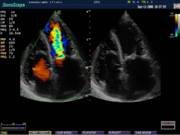

В Центре современных медицинских технологий «АКВА МЕД МАРИН» проводится УЗИ-диагностика на новейших ультразвуковых диагностических сканерах Экспертного класса SonoScape S40Exp и Премиум класса Toshiba SSA-780A, в том числе и УЗИ детям с применением специальных детских датчиков. Цветной допплер помогает точной диагностике патологии сосудов и сердца у взрослых и детей.

Компания SonoScape уделила особое внимание допплеровским режимам и является экспертом в своем классе, что позволяет с легкостью, но в то же время с уникальной точностью проводить исследования с постановкой наиболее точного диагноза.

Ультразвуковые исследования, доплеровское сканирование сосудов в Центре современных медицинских технологий «АКВА МЕД МАРИН» выполняется при помощи первого и единственного аппарата в Керчи SonoScape S40Exp (экспертного класса, который оснащен множеством новейших функций, многократно улучшающих качество и информативность УЗИ-исследования).